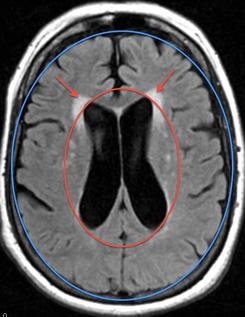

Normal Pressure Hydrocephalus (NPH) is caused by a pressure gradient in the spinal fluid-producing regions of the brain known as the "ventricles" and is depicted in the MRI picture to the right as the dark region within the red oval.  The ventricles are much larger than normal.  This enlargement of the ventricles may be see with aging, but when such enlargement is due to aging, we should also see a lot of spinal fluid (dark areas) outlining the sulci (indentations of the outer surface of the brain), depicted in the picture to the right as just within the blue oval.  When the degree of expansion (enlargement) of the ventricles (dark area within the red oval) is out of proportion to the degree of cortical (outer brain surface) atrophy (dark indentations just within the blue oval) expected, then we must consider hydrocephalus, or in this case, normal pressure hydrocephalus (NPH).  Additional findings on MRI include "transependymal flow", that is changes in the brain signal (white fluffy regions) surrounding the ventricles depicted by the red arrows in both MRI pictures.